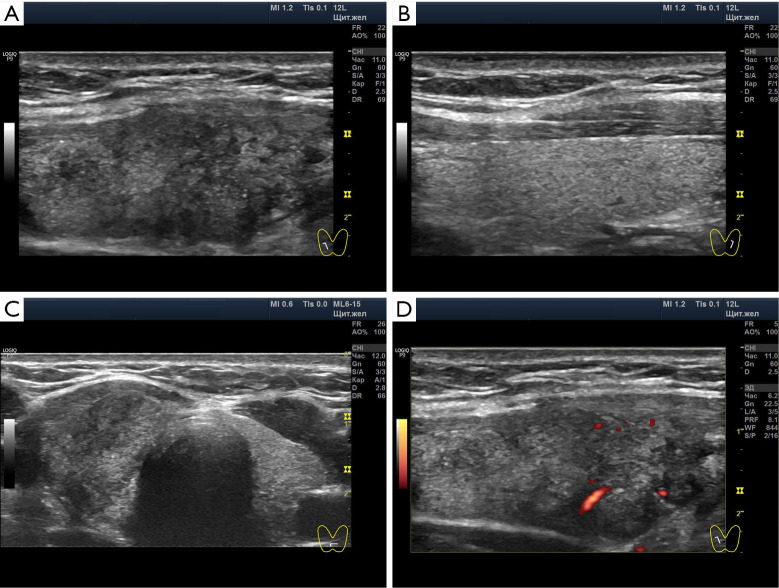

Case description: This case of unilateral PT in a pregnant woman has become an illustrative example for revising the idea of its pathogenesis. Laboratory data did not show obvious signs of inflammation, which is typical for pregnant women and does not exclude ST. At the same time, rare in the literature illustrations of the ultrasound picture of unilateral PT are shown. Pathological parallels with other unilateral thyropathies have been drawn. A possible source of unilateral thyroid changes may be the nerve-conducting mechanism.